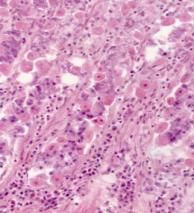

Под эпителием (в подэпителиальной зоне) в

складках желудка отмечаются диффузно

рассеянные клетки лимфоидного ряда, плотность распределения которых на

стандартной площади среза неоднородна. Менее всего этих клеток встречается в

1-м и 2-м зрелых возрастах (15,5 и 17,6 клеток) и более всего их - в пожилом

возрасте (42,8 клеток, на единице площади срезав 880 мкм²).

В

подэпителиальной зоне основную долю клеток составляют деструктивно измененные и

разрушенные клетки (рис.1), содержание которых практически одинаково во все

возрастные периоды (от 27,38 % до 30,28 %, различия не достоверны). Отмечено практически равное распределение ретикулярных клеток (22,70% - 24,42%). В подэпителиальной зоне молодые формы клеток

выявлены только в пожилом возрасте (1,39% больших лимфоцитов). Плазматические

клетки отмечаются в равном числе в 2-м зрелом и в пожилом возрасте (12,70 и

11,70%) и менее всего их в 1-м зрелом возрасте (9,62%, рис.1). В подэпителиальной

зоне во 2-м зрелом возрасте отмечено более всего макрофагов, по сравнению со

старшими возрастными группами (11,99% против 4,85% и 4,59%) и больше содержание гранулярных лейкоцитов

(нейтрофилов и эозинофилов - 4,22%). В 1-м зрелом и пожилом возрасте эти клетки

(эозинофилы) встречаются значительно реже - 1,18% и 0,92%, соответственно.